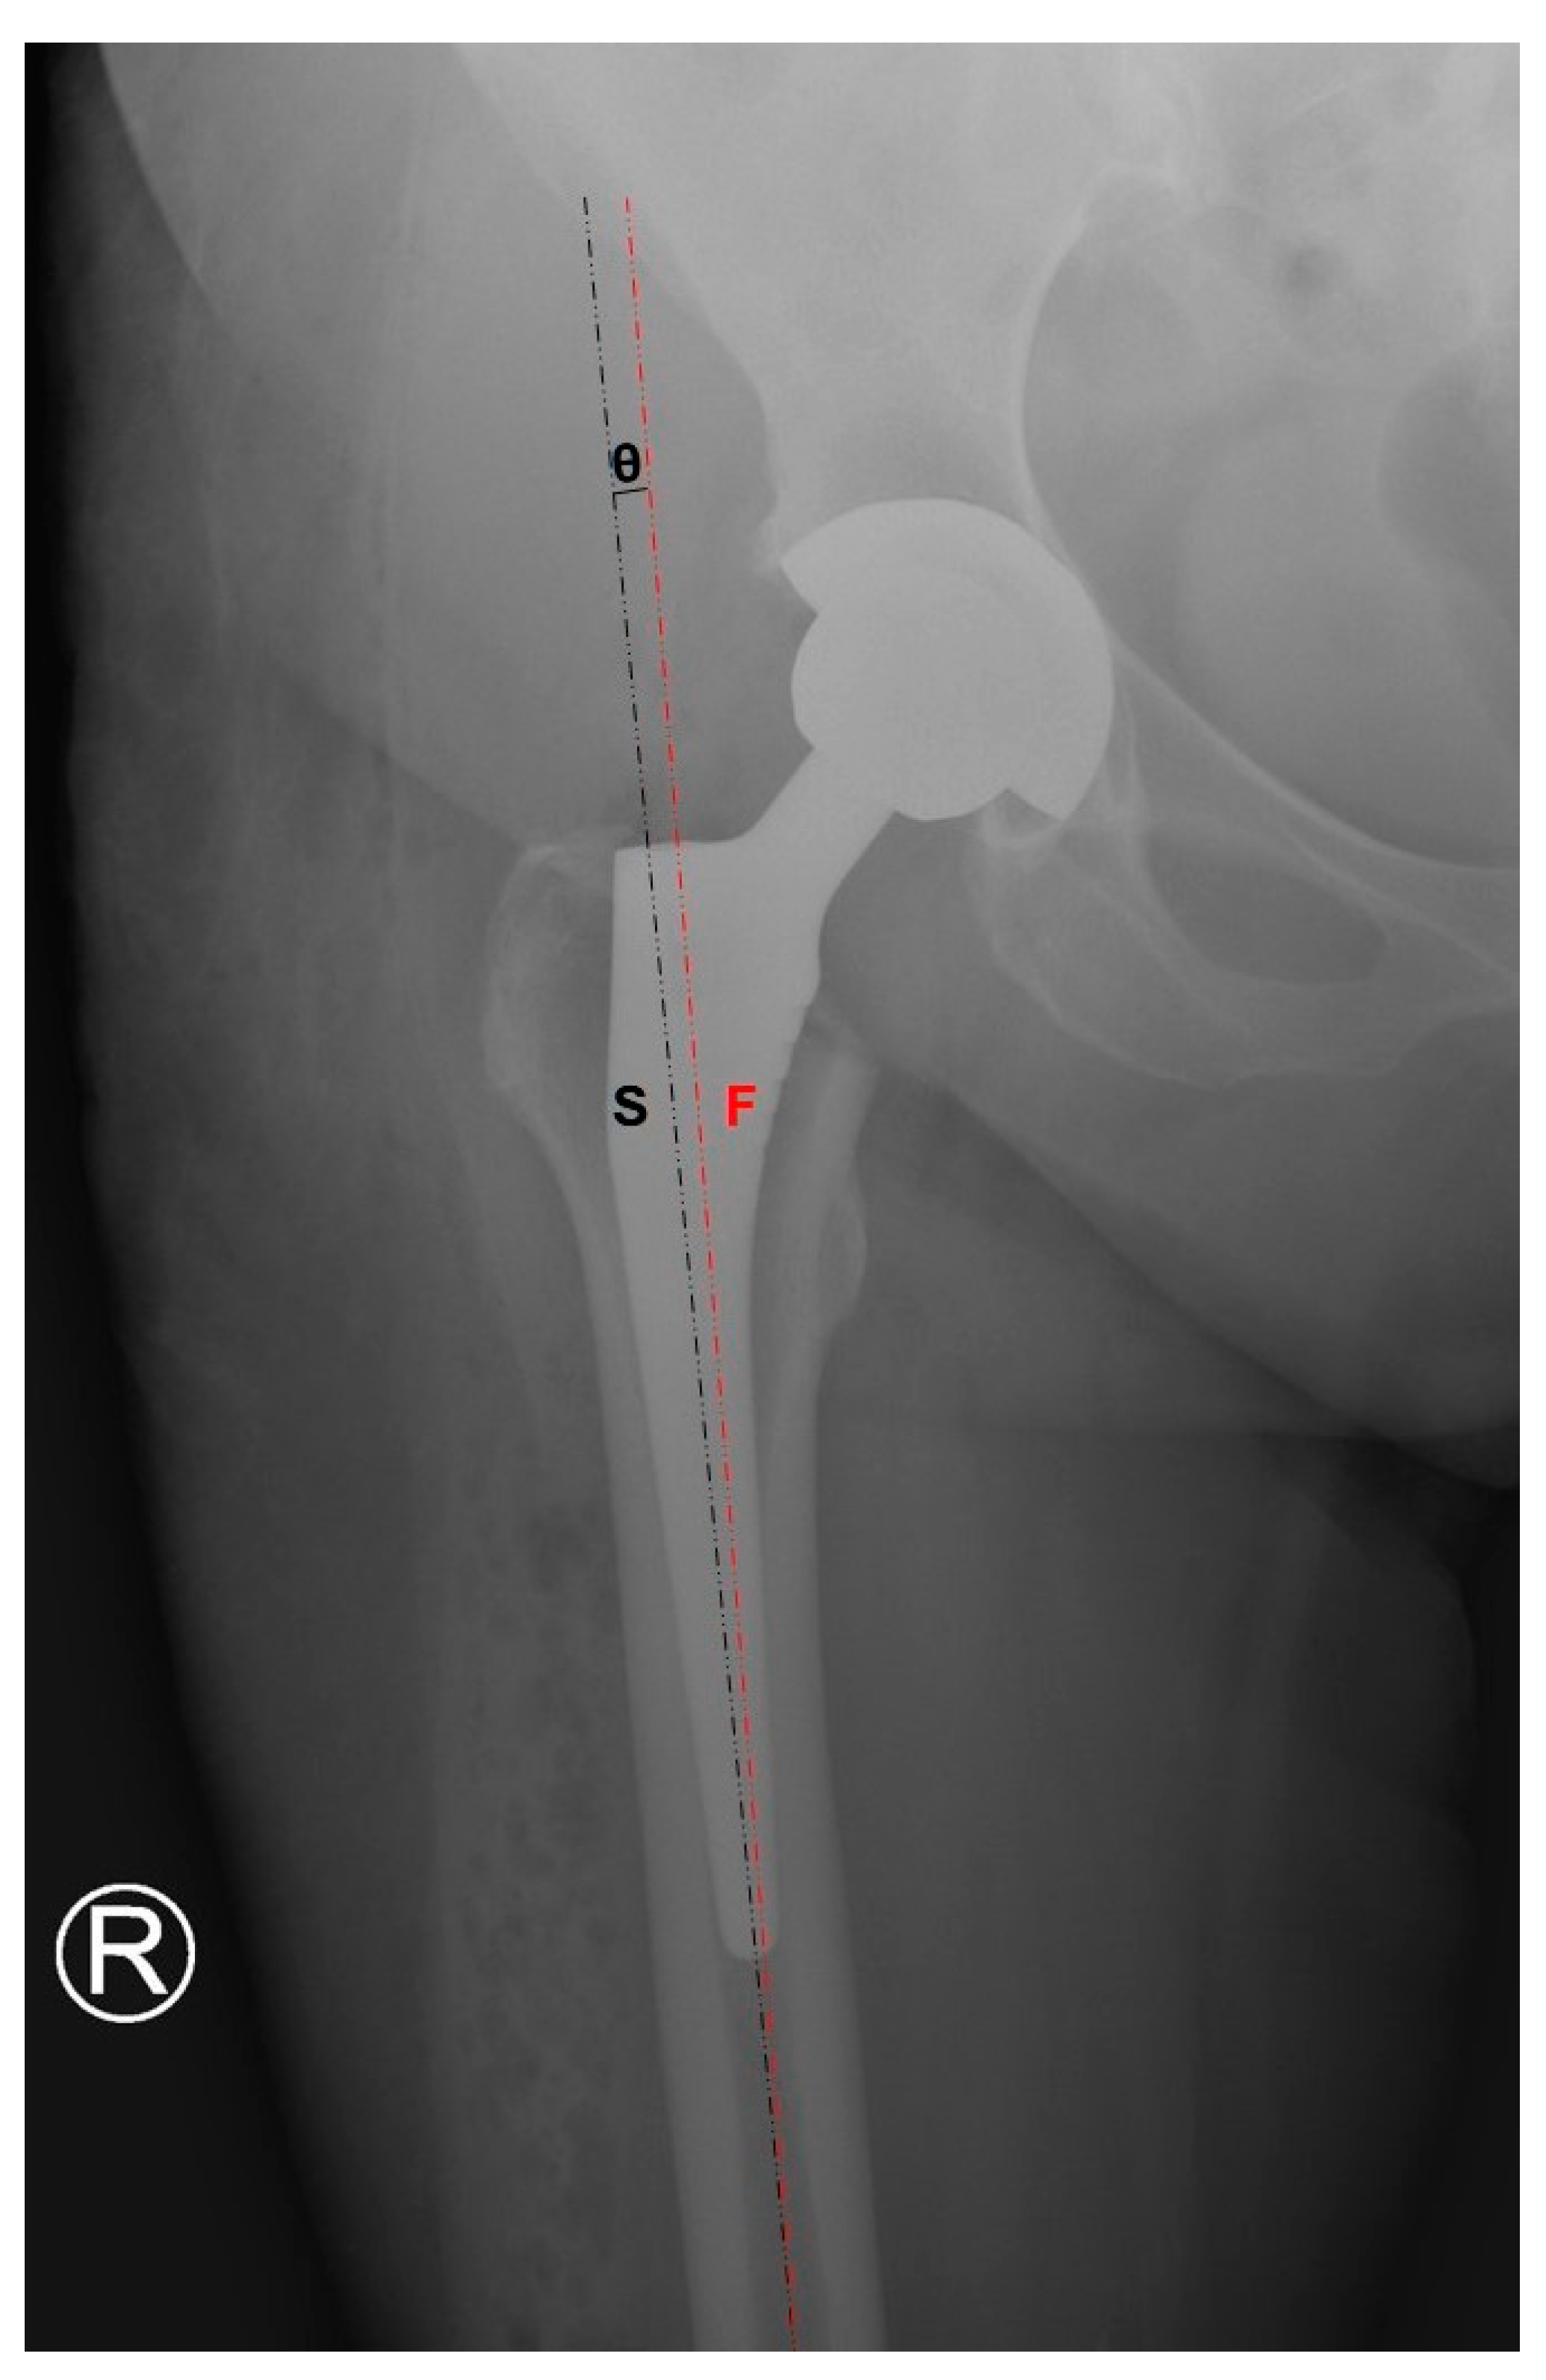

3.2. Femoral Stem Alignment

| Nistor [8], 2017 DAA vs. LA | 1.40° (SD 0.99°) varus | 1.29° (SD 1.13°) varus | ||

| Reichert [21], 2018 DAA vs. LA | 5.5% varus 2% valgus 92.5% neutral | 4% varus 2% valgus 94% neutral | ||

| Dienstknecht [22], 2014 DAA vs. LA | 2.6° (SD 2.1°) varus | 2.8° (SD 2.2°) varus | ||

| Cheng [23], 2017 DAA vs. PA | 1.09° varus | 1.62° varus | ||

| Barret [25], 2013 DAA vs. PLA | 2% varus 0% valgus 98% neutral | 26% varus 0% valgus 74% neutral | ||

| Taunton [24], 2014 DAA vs. PA | 4 varus/52 operated | 6 varus, 2 valgus/49 operated | ||

| Brun [28],2019 DAA vs. LA | 3.1° (SD 1.5°) varus | 2.9° (SD 1.1°) varus |